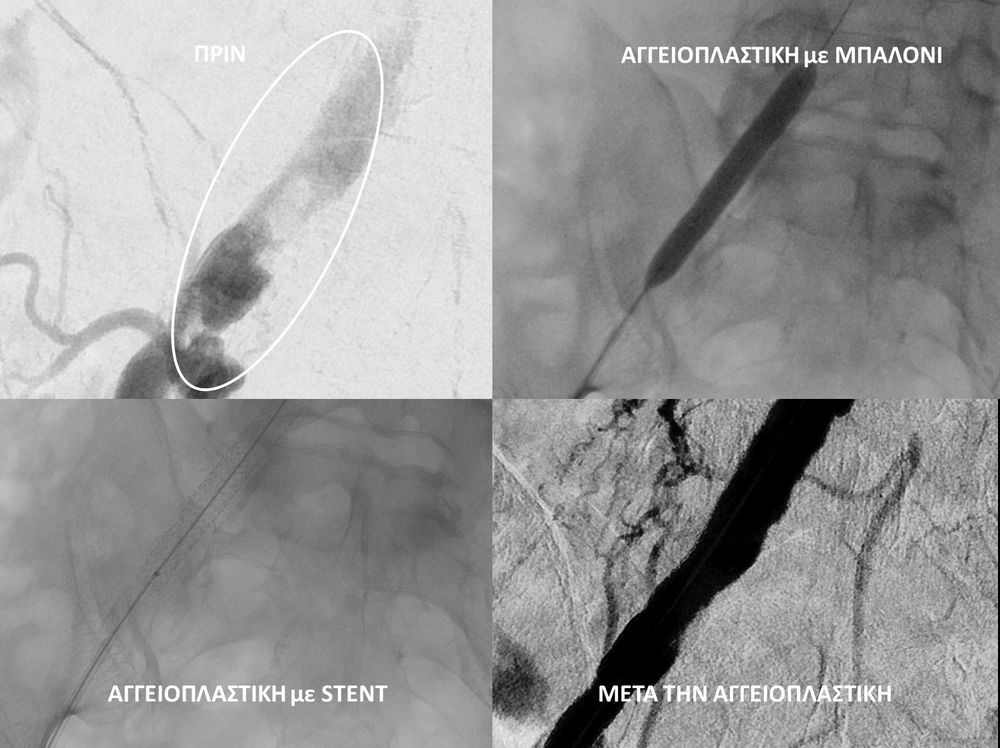

• Η αγγειοπλαστική των αρτηριών είναι μία μη χειρουργική επέμβαση που αποσκοπεί στη διάνοιξη των στενωμένων ή αποφραγμένων αρτηριών. Γίνεται με την ίδια τεχνική όπως και αγγειογραφία. Η αγγειοπλαστική των αρτηριών μπορεί να γίνει είτε με απλή διάνοιξη της αρτηρίας που εμφανίζει στένωση με μπαλόνι ή και να συνοδευθεί από τοποθέτηση ενδαγγειακής πρόθεσης (stent).